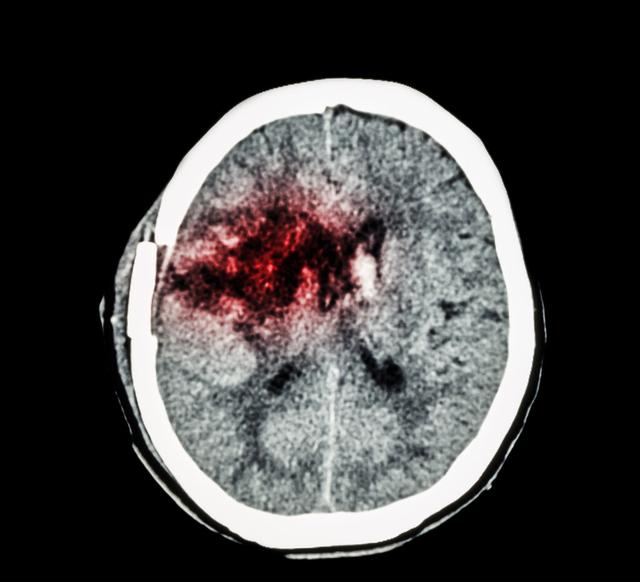

第种:脑出血

可以说,在高血压人群中,并发症是最高的,主要是由于血管弹性恶化和衰老引起的。